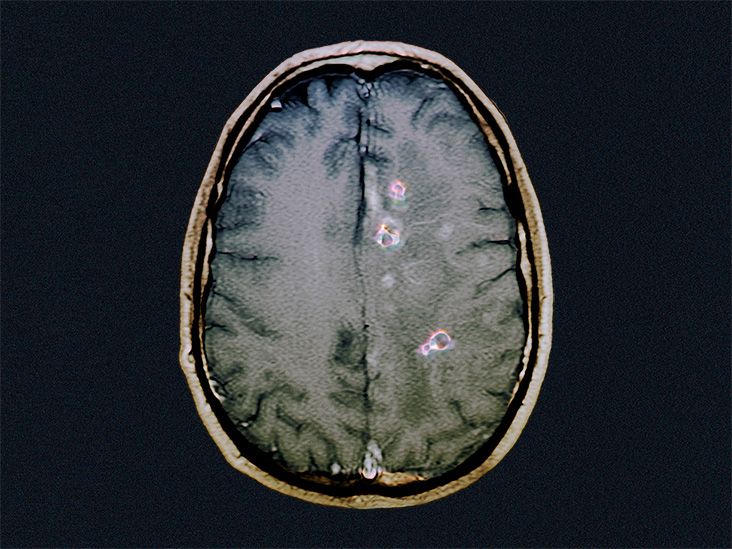

神経画像技術の進歩に伴い、神経嚢虫症の診断は近年より正確になってきました。

医師は、神経画像診断の結果を裏付けるために、抗体特異的な血液検査を使用することもあります。